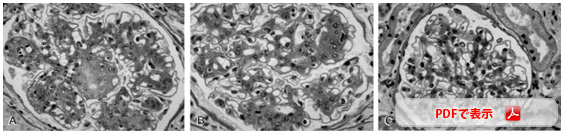

下の写真のように、早期腎症(微量アルブミン尿の時期)までに糖尿病を適切に治療すれば、糖尿病性腎症は改善することがわかっています。

A(左端)B(中央)が糖尿病性腎症の腎糸球体像

糖尿病の治療により正常の糸球体(C;右端)に回復する |

| (Fioretto P ら; N Engl J Med 339:65-75, 1998) |